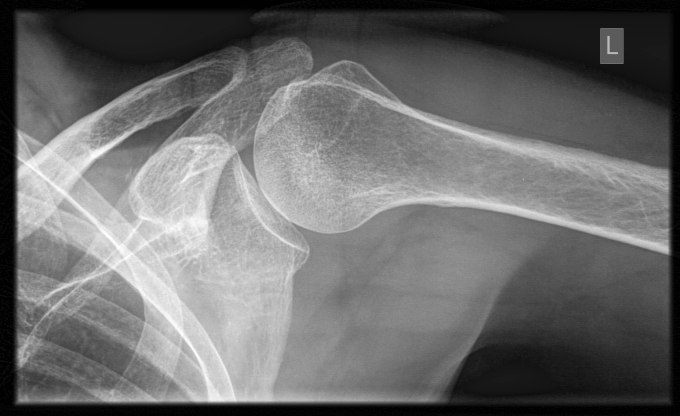

The shoulder joint is a ball and socket joint often likened to a golf ball sitting on a golf tee. The flat socket allows for great mobility, however as a trade-off, it lacks the stability seen in other joints around the body such as the hip joint. This lends itself to certain conditions which can cause pain and restriction. The shallow socket relies on cartilage surrounding its edges to increase its depth to improve stability. It is also very reliant on the surrounding structures working optimally to maintain correct joint alignment. Below lists the common causes of shoulder pain. Although this is not an exhaustive list, it does outline the more common conditions seen in the clinic.

• Shoulder dislocation/instability: when the head of the upper arm bone is forced out of the shoulder socket due to trauma. This then stretches or tears the ligaments and joint capsule causing them to loosen, and damages the cartilage that surrounds the joint

• Cartilage tear (labral tear): damage to the cartilage that surrounds the shoulder socket

• Osteoarthritis of the shoulder: degeneration of the cartilage which lines the bones in the joint